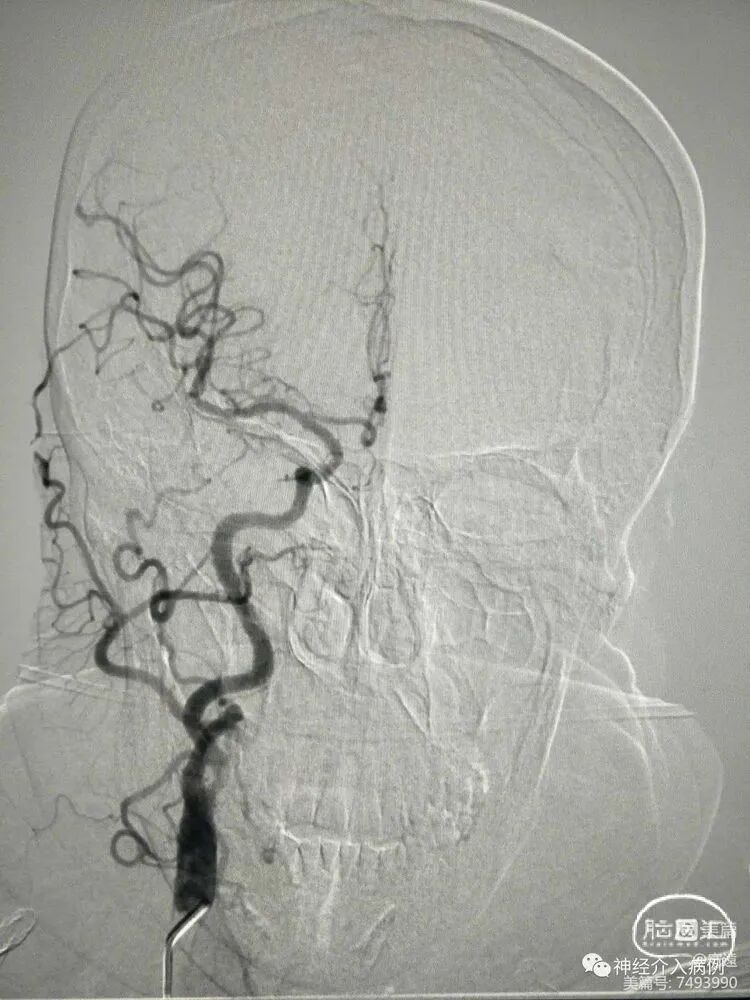

症状性右侧颈内动脉起始段重度狭窄性脑梗死(预扩张+锥形支架置入术)

DSA:前交通动脉未开放,右侧颈内动脉起始段重度狭窄伴溃疡斑块。